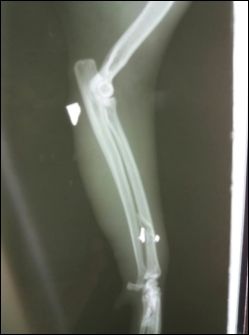

Am vom Arzt erstellten Röntgenbild waren die Patronen noch deutlich zu sehen. „Vermutlich war es ein Flobert-Gewehr", so die Tierschützerin und fügt im "Heute"-Gespräch hinzu: "Nicht nur Autos und Jäger setzen ihnen (Anm. den Tieren)zu, sondern auch Menschen, die ihnen nach dem Leben trachten!"